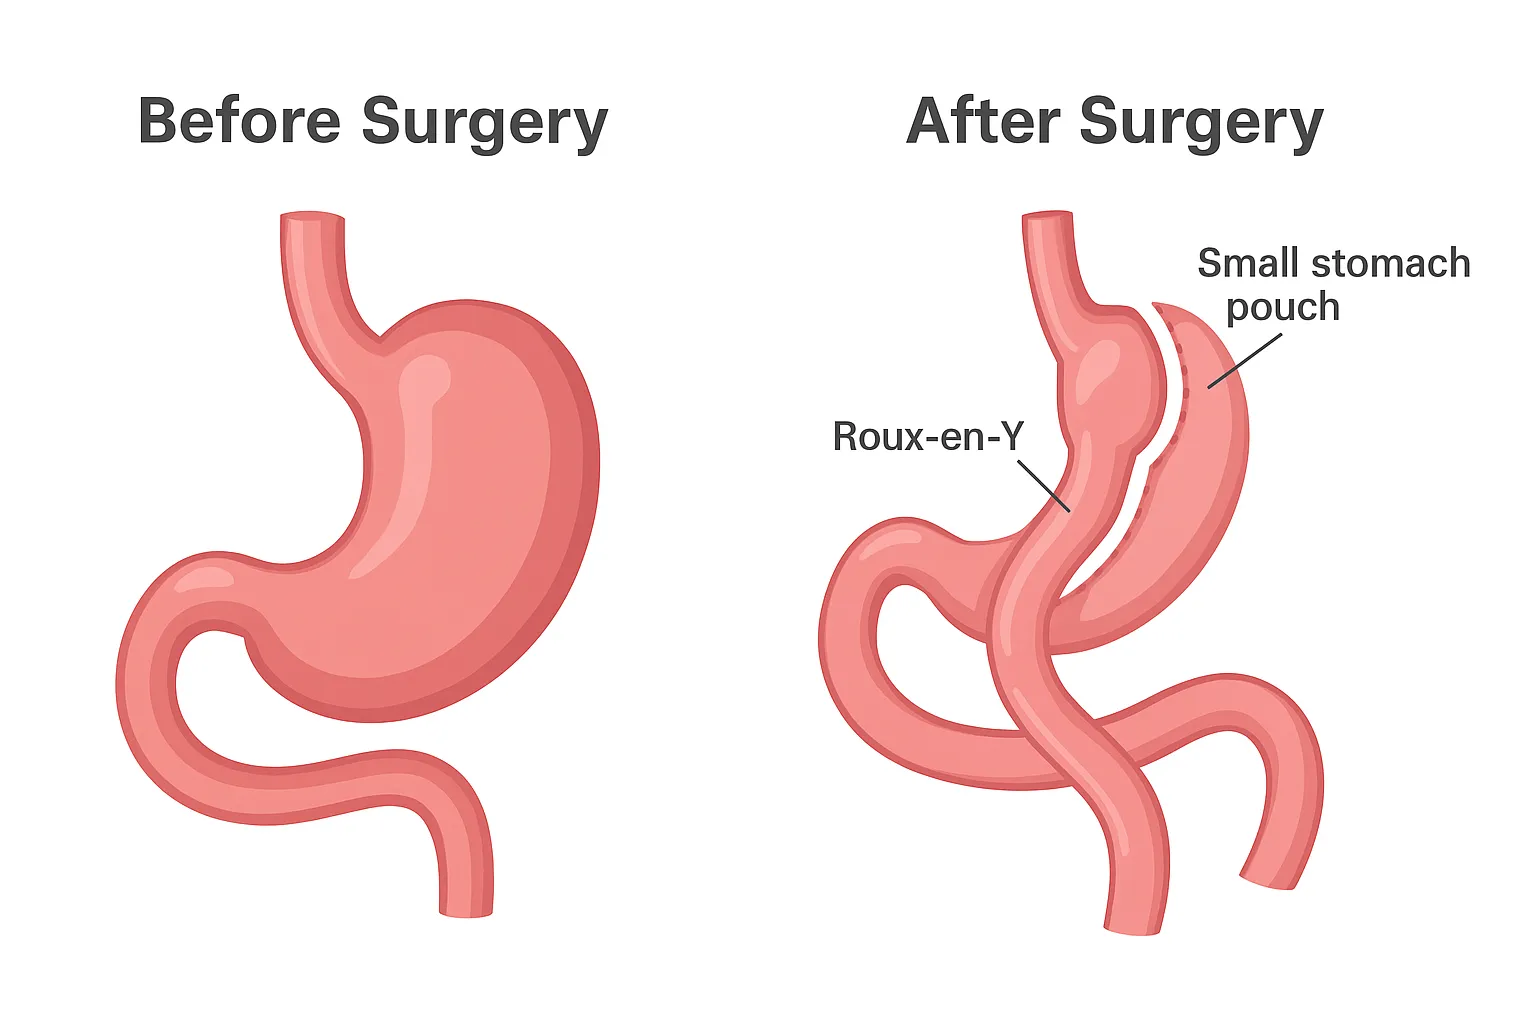

جراحی بایپس معده (Gastric Bypass Surgery یا Roux-en-Y Gastric Bypass) یک روش جراحی پیشرفته لاغری است که شامل دو تغییر اساسی در سیستم گوارشی میشود: اول، ایجاد یک کیسه کوچک از بخش بالایی معده (با حجم حدود ۲۰-۳۰ میلیلیتر) برای محدودیت مصرف غذا؛ دوم، بایپس (دور زدن) بخش باقیمانده معده و قسمت اولیه روده کوچک (دوازدهه و ژژنوم) با اتصال مستقیم کیسه معده به بخش میانی روده کوچک. این مکانیسم نه تنها حجم مصرف غذا را کاهش میدهد، بلکه جذب کالری و مواد مغذی را محدود کرده و تغییرات هورمونی (مانند کاهش گرلین و افزایش GLP-1) ایجاد میکند که اشتها را کنترل و متابولیسم را بهبود میبخشد. عمل بایپس معده به ویژه برای درمان چاقی مفرط (BMI بالای ۴۰) یا چاقی متوسط (BMI بالای ۳۵ با بیماریهای همراه مانند دیابت) مؤثر است و برخلاف روشهای موقتی، نتایج دائمی ارائه میدهد. دکتر محمدرضا مافی، بهترین جراح بایپس معده در تهران، این عمل را با تکنیک لاپاروسکوپی انجام میدهد تا حداقل تهاجم و حداکثر ایمنی را فراهم کند.

4. بایپس روده: بخش اولیه روده کوچک (دوازدهه) بایپس شده و کیسه معده مستقیماً به بخش میانی روده (ژژنوم) متصل میشود، ایجاد یک مسیر Y شکل (Roux-en-Y).